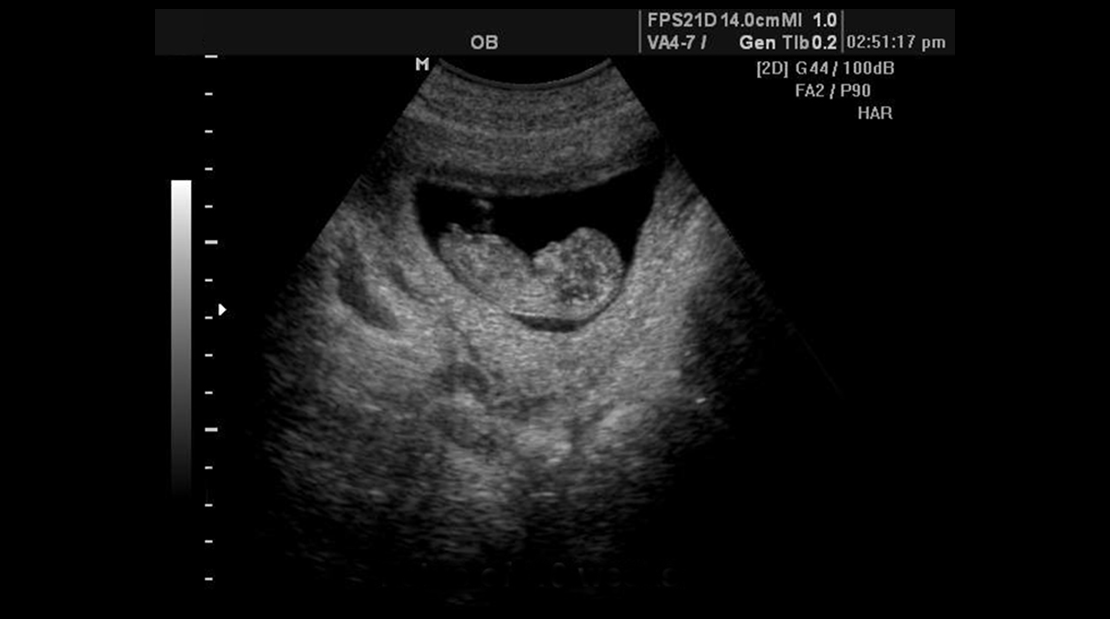

Полученное в ходе исследования изображение позволяет рассмотреть:

- положение плода;

- многоплодную беременность;

- состояние внутренних органов плода;

- гипотрофию;

- патологии внутриутробного развития ребенка;

- многоводие и маловодие (ненормальный объем амниотической жидкости);

- предлежание плаценты.